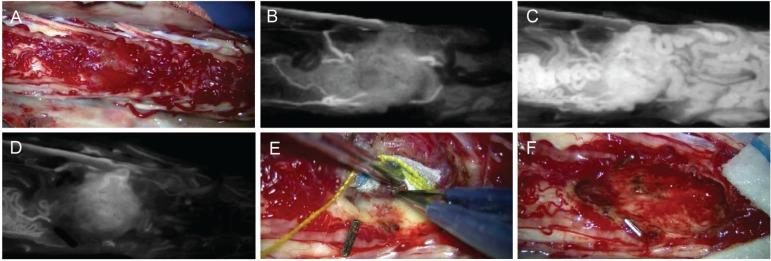

Surgery for spinal intramedullary tumors remains one of the major challenges for neurosurgeons, due to their relative infrequency, unknown natural history, and surgical difficulty. We are sure that safe and precise resection of spinal intramedullary tumors, particularly encapsulated benign tumors, can result in acceptable or satisfactory postoperative outcomes. General surgical concepts and strategies, technical consideration, and functional outcomes after surgery are discussed with illustrative cases of spinal intramedullary benign tumors such as ependymoma, cavernous malformation, and hemangioblastoma. Selection of a posterior median sulcus, posterolateral sulcus, or direct transpial approach was determined based on the preoperative imaging diagnosis and careful inspection of the spinal cord surface. Tumor-cord interface was meticulously delineated in cases of benign encapsulated tumors. Our retrospective functional analysis of 24 consecutive cases of spinal intramedullary ependymoma followed for at least 6 months postoperatively demonstrated a mean grade on the modified McCormick functional schema of 1.8 before surgery, deteriorating significantly to 2.6 early after surgery (< 1 month after surgery), and finally returning to 1.7 in the late postoperative period (> 6 months after surgery). The risk of functional deterioration after surgery should be taken into serious consideration. Functional deterioration after surgery, including neuropathic pain even long after surgery, significantly affects patient quality of life. Better balance between tumor control and functional preservation can be achieved not only by the surgical technique or expertise, but also by intraoperative neurophysiological monitoring, vascular image guidance, and postoperative supportive care. Quality of life after surgery should inarguably be given top priority.

由于脊髓髓内肿瘤相对少见、自然病史不明且手术难度大,其手术治疗仍是神经外科医生面临的主要挑战之一。我们确信,安全、精确地切除脊髓髓内肿瘤,尤其是包膜完整的良性肿瘤,可带来可接受或令人满意的术后结果。本文通过室管膜瘤、海绵状血管畸形和血管母细胞瘤等脊髓髓内良性肿瘤的实例,探讨了一般手术概念与策略、技术考量以及术后功能结果。根据术前影像诊断和对脊髓表面的仔细检查,决定选择后正中沟、后外侧沟或经皮质直接入路。对于包膜完整的良性肿瘤,要仔细勾勒肿瘤与脊髓的界面。我们对24例连续的脊髓髓内室管膜瘤患者进行了回顾性功能分析,这些患者术后至少随访6个月,结果显示术前改良麦考密克功能量表平均评分为1.8,术后早期(术后<1个月)显著恶化至2.6,术后晚期(术后>6个月)最终恢复至1.7。术后功能恶化的风险应予以认真考虑。术后功能恶化,包括术后很长时间仍存在的神经性疼痛,会显著影响患者的生活质量。不仅通过手术技术或专业知识,还通过术中神经生理监测、血管影像引导和术后支持治疗,可在肿瘤控制和功能保留之间实现更好的平衡。术后生活质量无疑应被置于首位。